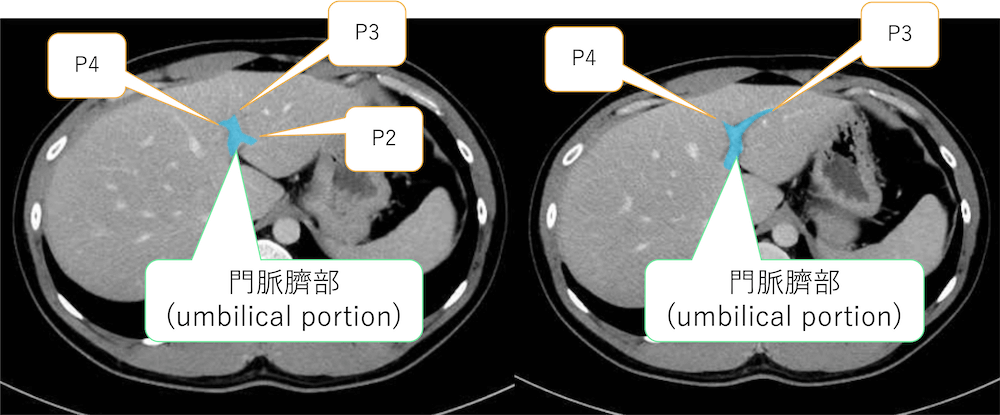

門脈が肝鎌状間膜の内部を走行する部分を臍部(umbilical portion)と言います。

ここから下の図のように肝S2,3,4の門脈であるP2,3,4が分岐します。

「ここから下の図のように肝S2,3,4の門脈であるP2,3,4が分岐します。」

の下のCTに記載があるP2とP3は逆の可能性ありますでしょうか。腹側がP3で背側がP2になるのかなと思いました。